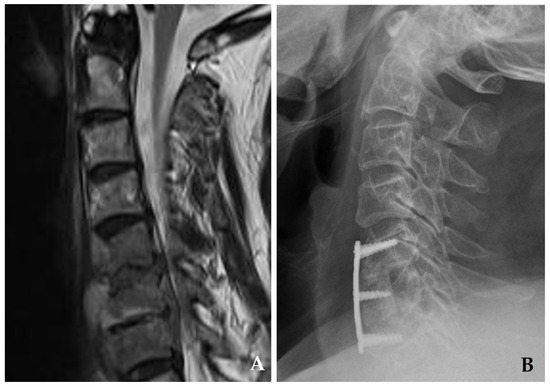

Preferred for 1–2-level disc space infections without significant vertebral body collapse. Allows for targeted debridement, interbody reconstruction, and early stabilization (Figure 3) [32,33].

Figure 3. Initial plain radiograph (A) and magnetic resonance imaging (B) demonstrate disc space narrowing at C4–C5 with retropharyngeal and epidural abscesses. The patient underwent C4–C5 discectomy with autograft, anterior plating, and posterior wiring (C), achieving solid fusion and complete resolution of spondylodiscitis at one year postoperatively.